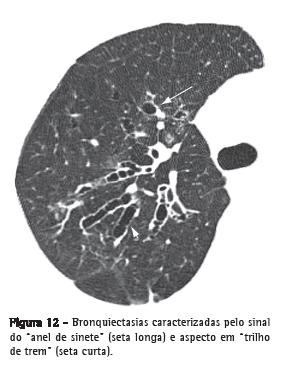

BronquiectasiaDilatação brônquica irreversível, que pode ser focal ou difusa. Geralmente decorre de infecção crônica, obstrução das vias aéreas proximais ou anormalidades brônquicas congênitas. Os achados morfológicos na TCAR (Figura 12) incluem o diâmetro interno do brônquio maior do que o da artéria pulmonar adjacente (sinal do anel de sinete); a perda do afilamento gradual do brônquio, definido como a manutenção do calibre por mais que 2 cm, distal à bifurcação (aspecto em "trilho de trem"); e a identificação de via aérea a menos de 1 cm da superfície pleural.

Bronquiectasias são frequentemente acompanhadas de espessamento das paredes brônquicas, impacção mucoide e alterações de pequenas vias aéreas.(26,27) A patologia define três tipos de bronquiectasia, a depender da aparência do brônquio acometido: cilíndrica, varicosa e sacular (ou cística).

Ver também Sinal do anel de sinete.

Sinal do anel de sinete

Sinal composto por uma opacidade anelar, que representa um brônquio dilatado, em associação com uma opacidade arredondada menor, contígua a sua parede, representando sua artéria (pulmonar ou raramente brônquica) que lembra o aspecto de um "anel de sinete" ou "anel de pérola".(74) Corresponde ao sinal tomográfico básico de bronquiectasia (Figura 12).(26,75) Ocasionalmente, o sinal do anel de sinete pode também ser encontrado em doenças caracterizadas por uma redução anormal do fluxo arterial pulmonar, tais como no tromboembolismo pulmonar crônico e na interrupção proximal da artéria pulmonar.(76)

Ver também Bronquiectasia.